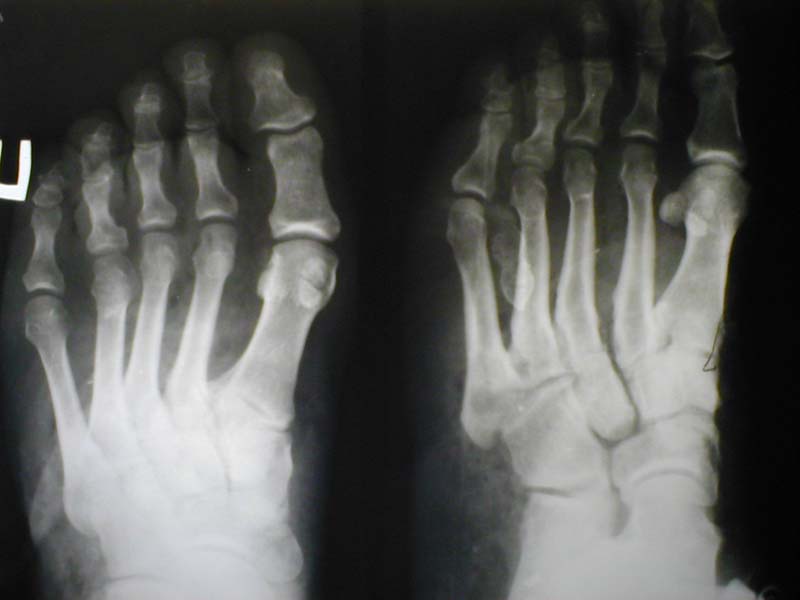

Мужчина, 48лет. Производственная травма (на стопу упал груз весом 2 тонны+химический ожог щелочью). Диагноз: комбинированная травма правой стопы, обширная рвано-скальпированная рана, химический ожог II ст. до 1% поверхности тела, закрытый перелом ладьевидной и I клиновидной костей. Ургентно произведено: ПХО, дренирование, иммобилизация задней гипсовой лонгетой; назначено: обезболивание, реополиглюкин, цефазолин, метрогил, курс ГБО. Вопрос: тактика лечения (дополнения и проч.)?Заранее благодарен! Фото 1 Фото 2 Фото 3 Фото 4 С уважением,А.В.ВладзимирскийДонецкий НИИ травматологии и ортопедииДонецк, Украина

5). Спасибо за подробную презентацию случая. Удивительно, что от 2 тонного груза столь незначительные костные повреждения. Видимо, основная тяжесть обусловлена разможжени-ем и химическим ожогом мягких тканей, компрометирующее перфузию дистального отдела стопы, возможное развитие компартмент синдрома. Если есть возможность выполнить ан-гиографию, то это бы определило дальнейший прогноз и тактику лечения. В нашем госпита-ле пока это недоступно и для оценки перфузии я пользуюсь пульс-оксиметром, сравнивая показатели поврежденной стопы и здоровой. На представленных фотографиях кожный лос-кут на тыльной поверхности стопы явно нежизнеспособен, поэтому подшивать его я бы не стал. При выполнении первичной хирургической обработки я бы иссек нежизнеспособные ткани, продольными разрезами декомпрессия межкостных пространств и первичная кожная